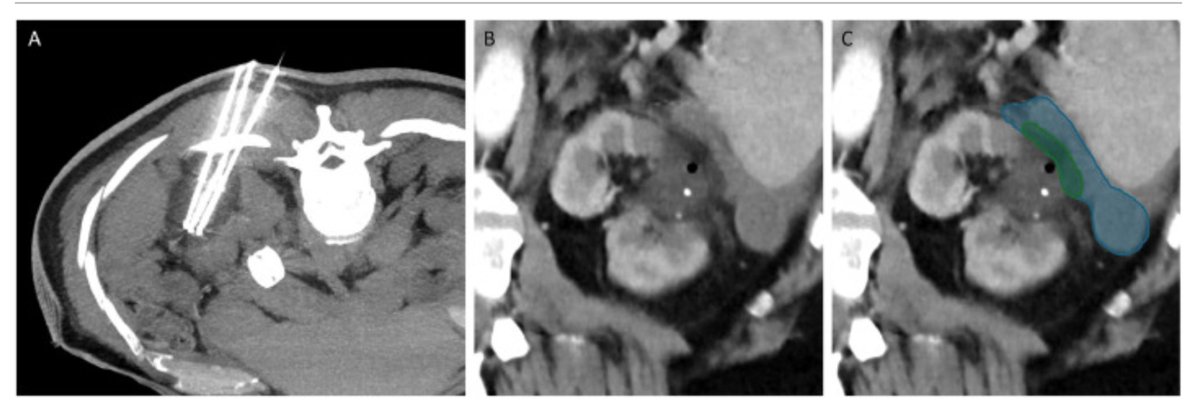

Interventional Radiology has a leading responsibility for patients with #HCC.

Congrats to my colleague @FZIslamMD for leading our latest pub, which highlights the importance of multidisciplinary management for HCC + the critical footprint of Interventional Radiology across multiple timepoints. 📝 dovepress.com/real-world-ana… @BeauToskichMD @MayoClinicFL_IR